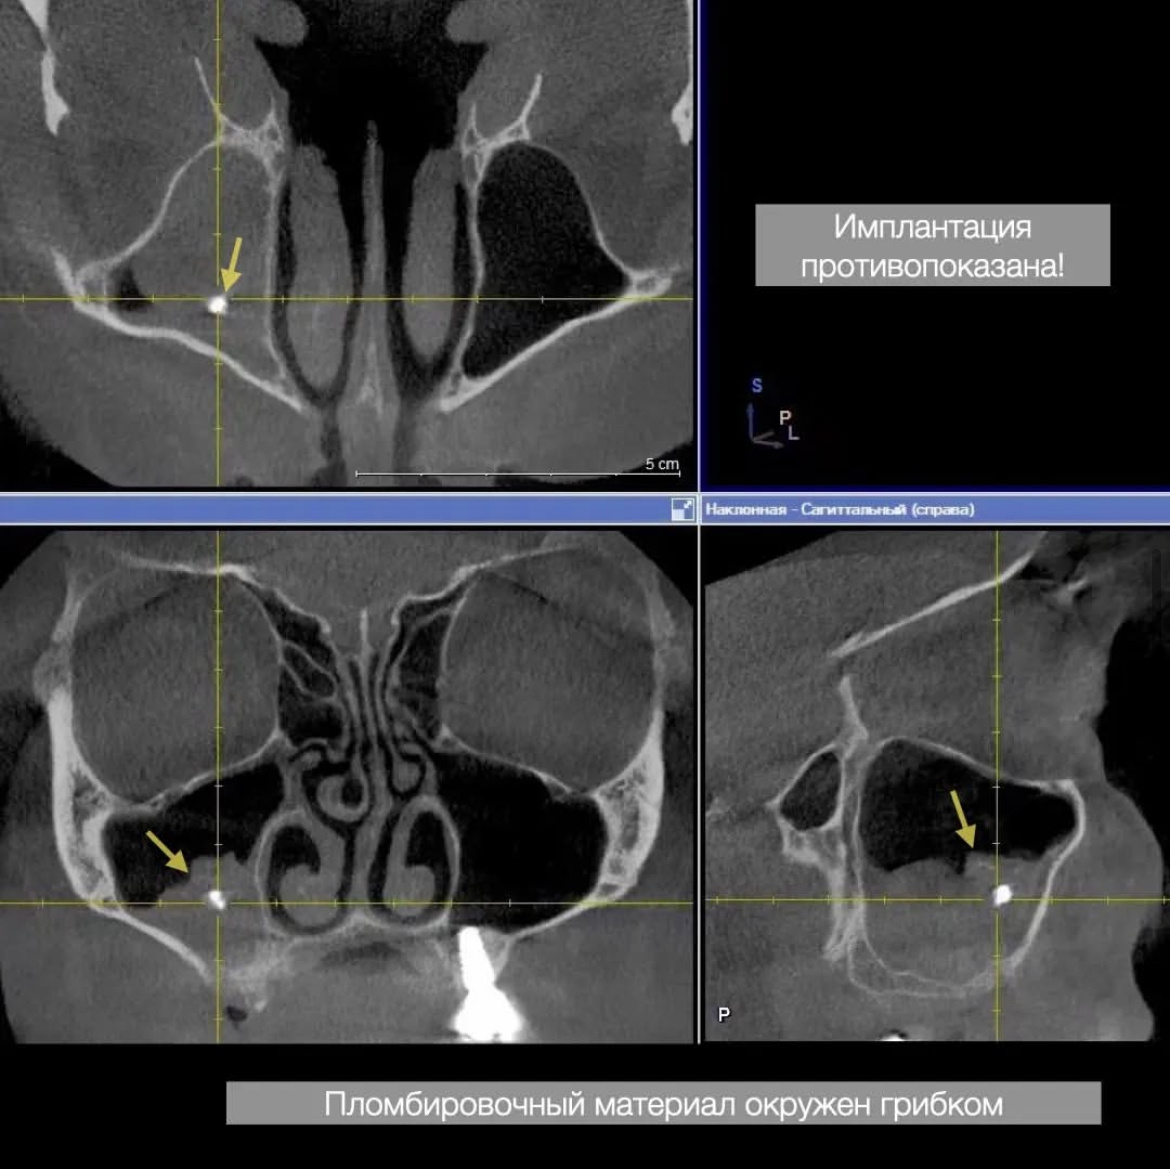

Инородное тело (пломбировочный материал) в пазухе - хирургические манипуляции противопоказаны

Два месяца после санации пазухи у ЛОР-врача - можно проводить имплантацию